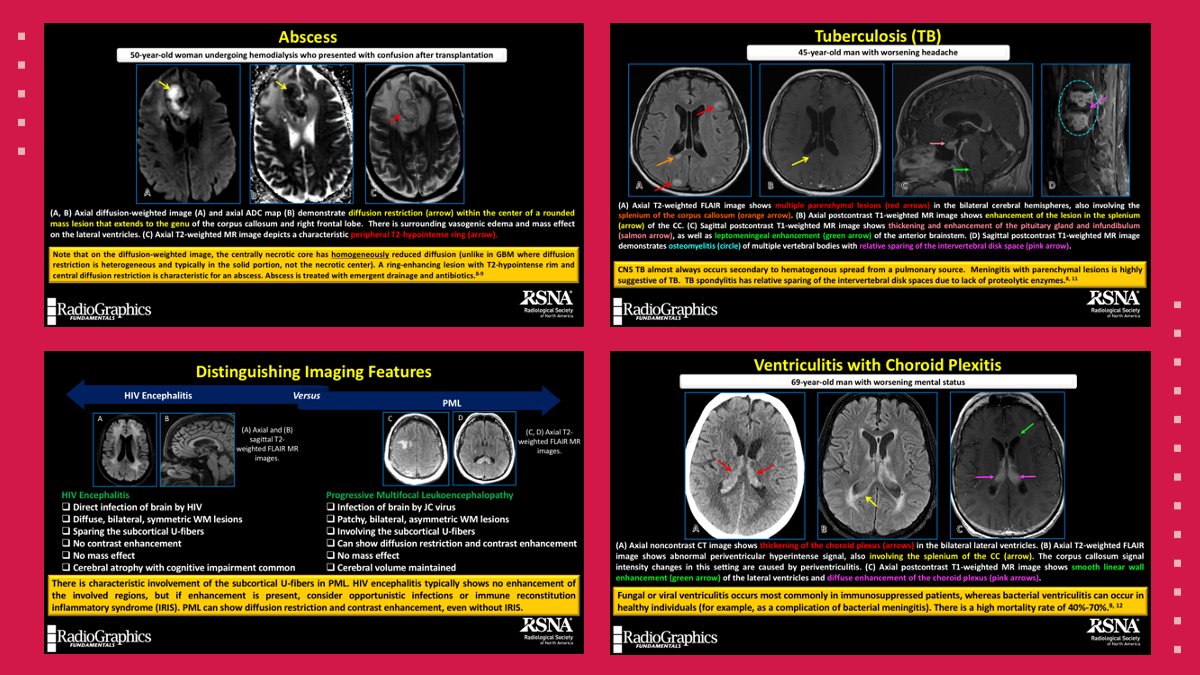

A variety of infectious etiologies can affect the corpus callosum, including pyogenic abscess, tuberculosis, and HIV.

#RGphx